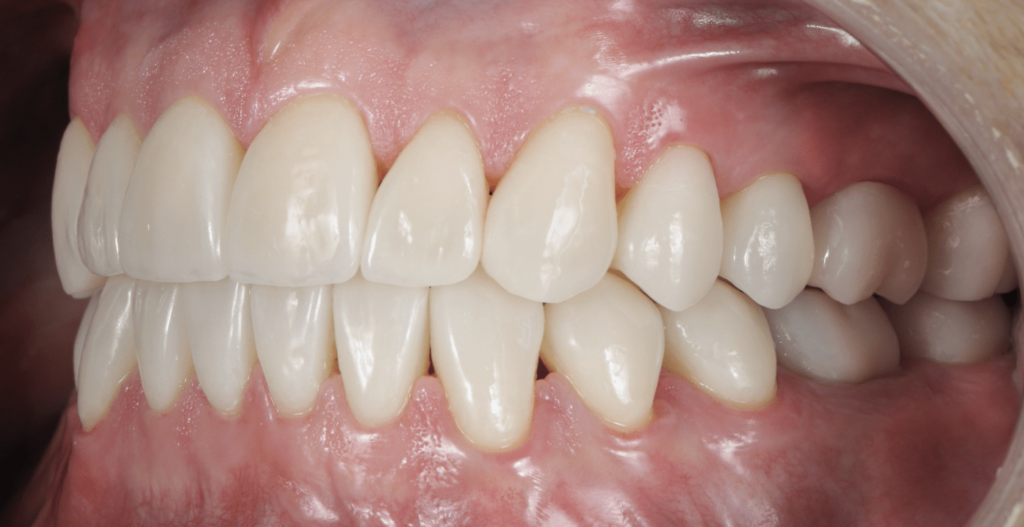

Occlusion Statique : Relations Interarcades

Surplomb et Recouvrement

Le surplomb (overjet) : projection dans le plan horizontal de la distance entre les sommets cuspidiens ou les bords libres. Normalement compris entre 1 et 3 mm.

Le recouvrement (overbite) : projection dans le plan vertical de la distance entre les bords libres des incisives. Physiologiquement de l’ordre du tiers de la hauteur coronaire incisive.

Ces deux paramètres définissent les rapports spatiaux entre les arcades au repos.

Classification d’Angle : Évaluer les Malocclusions

La classification d’Angle, établie au début du XXe siècle, demeure la référence pour décrire les relations sagittales des arcades. Elle se fonde sur le rapport entre la première molaire inférieure et la première molaire supérieure, s’appliquant par extension aux canines.

Classe I d’Angle (Normocclusion)

La cuspide mésio-vestibulaire de la première molaire supérieure s’engage dans le sillon vestibulaire de la première molaire inférieure. La pointe canine supérieure se situe dans l’embrasure entre la canine inférieure et la première prémolaire inférieure.

Cette classe représente la relation occlusale idéale sur le plan sagittal.